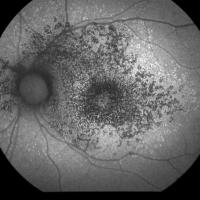

An eye doctor can check for Stargardt disease as part of a dilated eye exam. The exam is simple and painless — your doctor will give you some eye drops to dilate (widen) your pupils and then check for signs of Stargardt disease, like yellowish flecks on your macula.

• Fundus photography. Your eye doctor may take a photo of your retina to check for yellowish flecks on your macula.